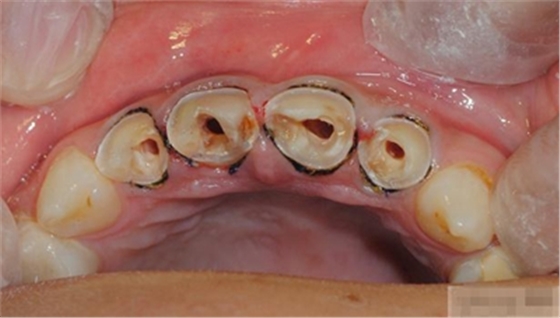

【檢查】12,11,21,22,均行玻璃離子充填,各牙不同程度部分充填物脫落,探(—),叩(—),冷刺激無(wú)反應(yīng),無(wú)松動(dòng),牙齦顏色粉紅,質(zhì)地堅(jiān)實(shí)而有彈性,點(diǎn)彩正常,牙結(jié)石(—);牙髓活力測(cè)試無(wú)反應(yīng)。

【診斷】12,11,21,22牙體缺損

充填初步完成

【初步修整】

對(duì)于唇面,首先使用火焰狀車針進(jìn)行修整,一般不使用輪狀車針修整線角

微細(xì)的表面結(jié)構(gòu)最后使用鎢鋼拋光車針成形的。

【充填完成】

1、樹(shù)脂貼面平齊牙齦邊緣是最佳設(shè)計(jì),或者使用齦上邊緣 。

2、釉質(zhì)邊緣要用橡皮輪拋光。拋光可以去除懸釉。這樣經(jīng)過(guò)車針打磨過(guò)的釉質(zhì)表面會(huì)更加均一,形成良好的邊緣封閉。

3、纖維樁通常深入到根管的1/2至2/3處。因?yàn)樽罴训恼辰有Чl(fā)生于根管的冠1/3和中1/3。由于根1/3的牙本質(zhì)小管往往不能充分敞開(kāi),此區(qū)域幾乎沒(méi)有粘接作用發(fā)生,所以,根管纖維樁放置的深度無(wú)需超過(guò)根中1/3。